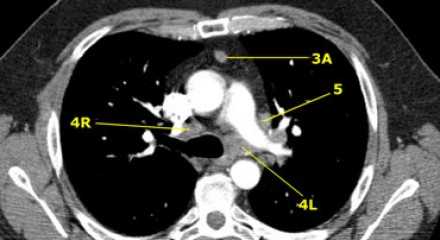

На левом изображении над уровнем легочного ствола представлены нижние паратрахеальные узлы слева и справа, так же здесь представлены узлы 3 и 5 групп.

Изображение слева выше уровня карины. Слева от трахеи 4L узлы. Обратите внимание что они расположены между легочным стволом и аортой, но не в аортопульмональном окне, потому что они лежат медиальнее артериальной связки. Лимфатические узлы латеральнее легочного ствола относятся к 5 группе.

- 5. Субаортальные лимфатические узлы

- Субаортальное или аортопульмональное окно расположено кнаружи от артериальной связки и проксимальнее первой ветви левой легочной артерии и лежит в пределах медиастинальной плевры.

- Парааортальные лимфатические узлы лежат кпереди и кнаружи от восходящего отдела аорты и между верхним и нижним краями дуги аорты.